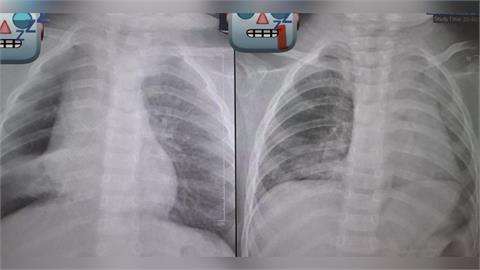

阿嬤餵孫整顆花生「卡氣管3天長肉芽」!見「肺塌陷」險喪命⋯醫師發文怒斥